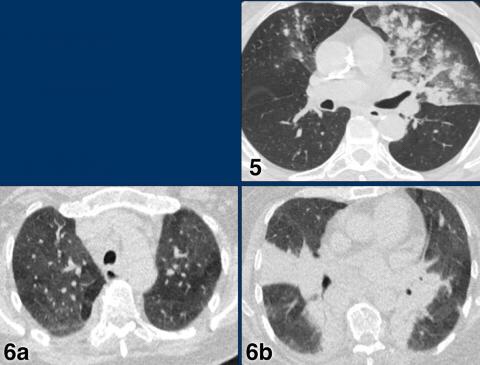

CORADS 4

In CO-RADS 4 the level of suspicion is high.

Mostly these are suspicious CT findings but not extremely typical:

• Unilateral ground glass

• Multifocal consolidations without any other typical finding

• Findings suspicious of COVID-19 in underlying pulmonary disease.

Case 1

7 days of compaints

CT: unilateral areas of GGO in left upper lobe.

PCR: positive.

Case 2

CT: bilateral GGO in a patient with emphysema.